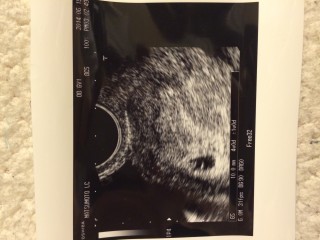

前回4週目の時は何にもみえなかったのでチョット不安でした☆ 胎芽みえるかなと思いきや、今回は胎嚢のみ;^_^A

またも不安ですが、次回はちゃんと赤ちゃん見えてるからねと先生が言ってくれました☆ツワリがはじまり具合悪いけど、楽しみにしてます☆

6w1d 22mm